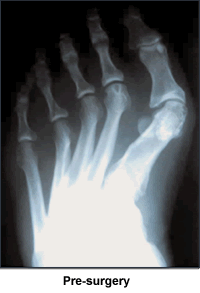

I was born with bunions. When I was 12 years old, my mother took me to a podiatrist for help. He said I was too young, and come back when I'd finished growing. So when I was 23 and had my own health coverage, I went to an orthopedic surgeon by myself. Now I didn't just have 2 little bunions. My toes were all crooked. My big toes went out at sharp 45 degree angles before coming back in. The doctor agreed both feet needed surgery, one just for cosmetic reasons if nothing else. So he sawed off the bunions and lengthened the ligaments between the big and 1st toes on both feet. On my left foot, he also broke the big toe and tried to turn the bone back in at a more appropriate angle. After much pain and recuperation, I decided my feet were "fixed".

Unfortunately, though, if I stood for long periods of time during the day, by the time I would lie in bed at night, it felt as if someone was hitting the soles of my feet with a rubber hose. As I got older, my feet started changing, but not for the better. Both feet still had the big toes going out at 45-degree angles; the bone breaking did not help. My feet were getting wider, the toe area was splayed, but the toes themselves angled into a point at the end of my feet. One toe was starting to cross horizontally over another toe. I was aghast to realize that my toes were definitely turning into my mother's toes.

I felt foolish at the appointment, because my feet weren't particularly hurting, I hadn't had an accident and they were just my "normal" feet. Dr. Leavitt was amazed looking at the x-rays at how deformed my feet really were. He had such compassion and empathy and stressed how the operations would be major ones, but that he could really fix my feet from the metatarsal on. Not many doctors could do this. My first doctor definitely did not. When he broke my toe, he was putting a splint on the top of a tree that was crooked at the base (Dr. Leavitt's analogy). Dr. Leavitt said to take my time and think about it because I would be unable to use each foot for 8-10 weeks. A wave of shock and gratitude swept through me as I realized he was talking about giving me totally normal feet. I wanted to get started and shortly thereafter Dr. Leavitt operated on my first foot. Six months later, he operated on my other foot. I have a cast on as I write these words.